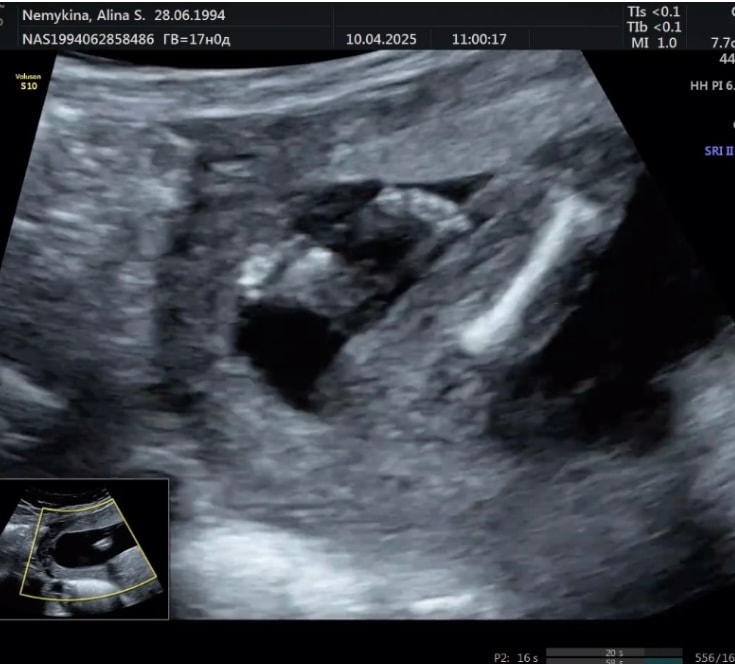

УЗИ 16-17 недель

это девочка на 99%

❆Elena❆, да я уверена была, сын. Уже и кое что ему купила… теперь в мае спрошу. Изображение Вот наверху дочка моя, внизу сейчас. Изображение А еще вот. Девочки мне сказали губы и клитор торчит